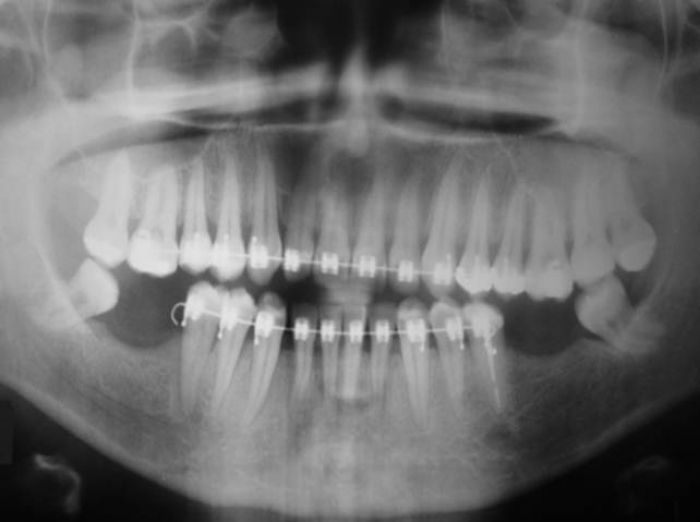

Raio X com próvisório já instalado sobre o implante cone morse

Imagem do caso finalizado em maio de 2012

Raio X de controle, realizado 05 meses após o término do tratamento